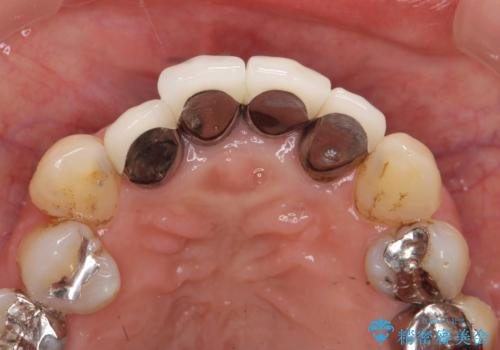

以前に治療した前歯クラウンは月日が経過することで劣化・歯肉の位置変化を引き起こし審美障害を引き起こしています。

劣化したクラウンを除去し、再発した虫歯を徹底的に除去したのち根管治療・ファイバーコア築盛を行いジルコニアクラウン製作へと移ります。